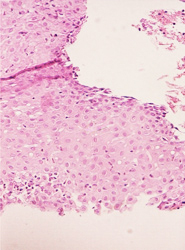

• NIC I.- Acantosis regular, anisocitosis y anisocariosis leves. Proceso inflamatorio en la lámina propia severo reactivo.

• NIC I.- No obstante la cariomegalia, la cromatina esta dispuesta en grumos finos.

• NIC I.- Anisocitosis y anisocariosis leves. Estroma ricamente vascularizado.